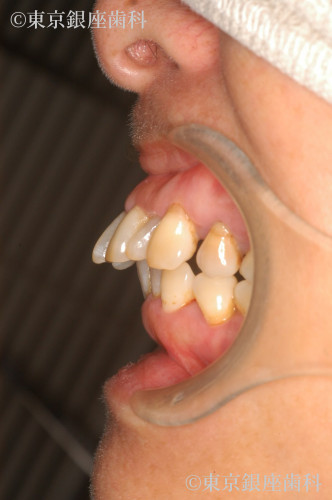

全顎的な重度歯周病による動揺、歯列崩壊をワンデイインプラントで改善した症例

全体的に歯がぐらつき出血し、何本か抜けてしまった。日に日に悪くなっている。他院で総入れ歯しかないと言われた。

全顎的に歯周病が進行し早急に抜歯が必要な歯が何本もあった。咬合改善、審美回復も望まれていたため全ての歯を抜歯し上下ワンデイインプラントを計画した。その際、左上顎洞部分の骨が薄いことから、人工骨を用いて骨量を増やしインプラントの安定を図るサイナスリフトも同時に行うこととした。